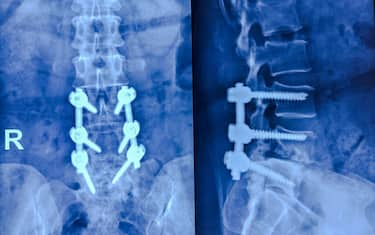

Spondilolistesi, che cos'è e quali sono i sintomi Salute e Benessere Le vertebre dei pazienti presentano un grado di micro-instabilità che impedisce la normale... 11 dic - 13:10